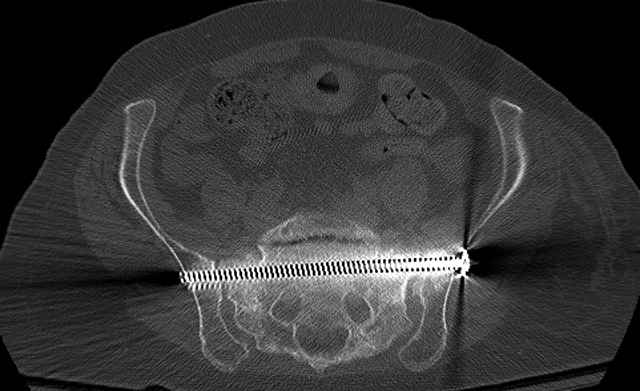

Pelvic CT Scan - 3 Months After Fall

Sacral Injuries

Percutaneous Fixation

(B) Ramus-Retrograde

2 TransIliac-TransSacral

Upper Segment